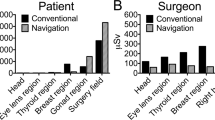

Both the SFII and FPD fluoroscope release ionizing radiation that can be harmful to not only the patient, but also the surgical team and staff12,13,14,15. Ionizing radiation can cause cellular damage while increasing risks for cancer, especially in the pediatric population16. The FPD fluoroscope has been shown to reduce the amount of radiation during central venous catheter placement and reduces the image distortion while increasing navigational accuracy in the pediatric population10,17,18, and has been used for dynamic chest X-rays, during a mechanical thrombectomy, and for brachytherapy in the adult population19,20,21. However, the FPD fluoroscope has not been studied in the field of hip preservation.

There was a 78% reduction in average total radiation dose in the FPD fluoroscope group, 91.12 mGy, compared to the SFII cohort, 410.61 mGy (p = 0.0001). There was also a 59% decrease in radiation exposure time between groups. There was a significant difference between the two cohorts for both radiation exposure dose and radiation exposure time (Table 3). The average radiation dose rate (mGy/second) was statistically different between the two groups. The SFII cohort averaged 0.44 mGy/second, while the FPD cohort averaged 0.24 mGy/second (p < 0.0001). This demonstrates the higher efficiency of the FPD machine that can lead to a decreased dose even when the overall fluoro exposure time is not significantly lower. Additionally, the average kV/mA for the SFII was 80.08/2.75 and the FPD was 76.41/0.69.

The average surgical time was significantly reduced in the FPD cohort, 6.74 ± 0.86 h, relative to the SFII cohort, 9.09 ± 1.44 h (p < 0.0001). Therefore, we also compared the average radiation dose per surgical hour between the two cohorts to decrease surgeon experience bias. Consistent with the primary analysis, the average radiation dose per hour of surgical time was significantly less in the FPD cohort, 13.63 mGy/hr ± 7.57, compared to the SFII cohort, 44.25 mGy/hr ± 20.13 (p < 0.0001). Each machine also measured the total radiation exposure time per case. We used this value to calculate the average radiation exposure time per surgical hour: 9.32 ± 1.60 min/hr (SFII) and 0.93 ± 0.15 (FPD, p < 0.0001), which was also significantly different between groups.

Reduction of radiation exposure to young patients and operating room personnel is of the utmost importance while maintaining the quality of surgical correction during PAO surgery. Previous literature has described the amount of radiation an orthopedic surgeon is exposed to intraoperatively. According to Canham et al., during an arthroscopic hip procedure there is an average radiation dosage of 490 mrem (4.9 mGy) to the surgeon25. We recognize that the PAO is a longer surgical procedure compared to a hip arthroscopy, but this is the closest comparable dose reporting thus far in the literature. We demonstrate in this single-institution retrospective review that the FPD fluoroscope has the potential to decrease direct radiation, including both exposure time, dose, and dose rate during PAO while maintaining a similar quality of surgical correction as compared to a traditional fluoroscope. Additionally there was a decrease in mA which suggests that the FPD uses less than half the mA compared to the SFII to achieve the same image quality. This explains the lower radiation dosage produced by the FPD due to the higher efficiency of the detectors that allows for fewer x-rays to get the same noise level.